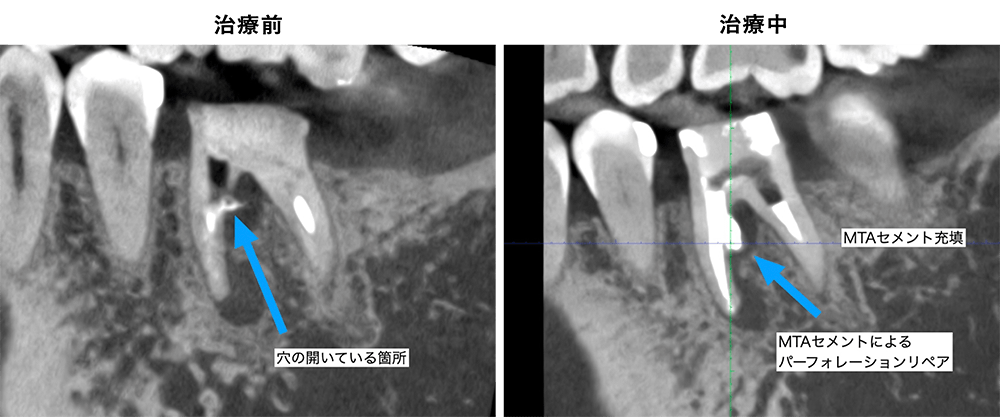

金山デンタルクリニックでは、治療の前に必ずCT撮影を行い、神経の本数や根の形、病変の大きさを正確に診査。治療の可能性や成功率まで含め、CTの画像を見せながら丁寧にご説明しています。治療後の経過もマイクロスコープやCT画像をお見せしながら、ご説明させていただきます。